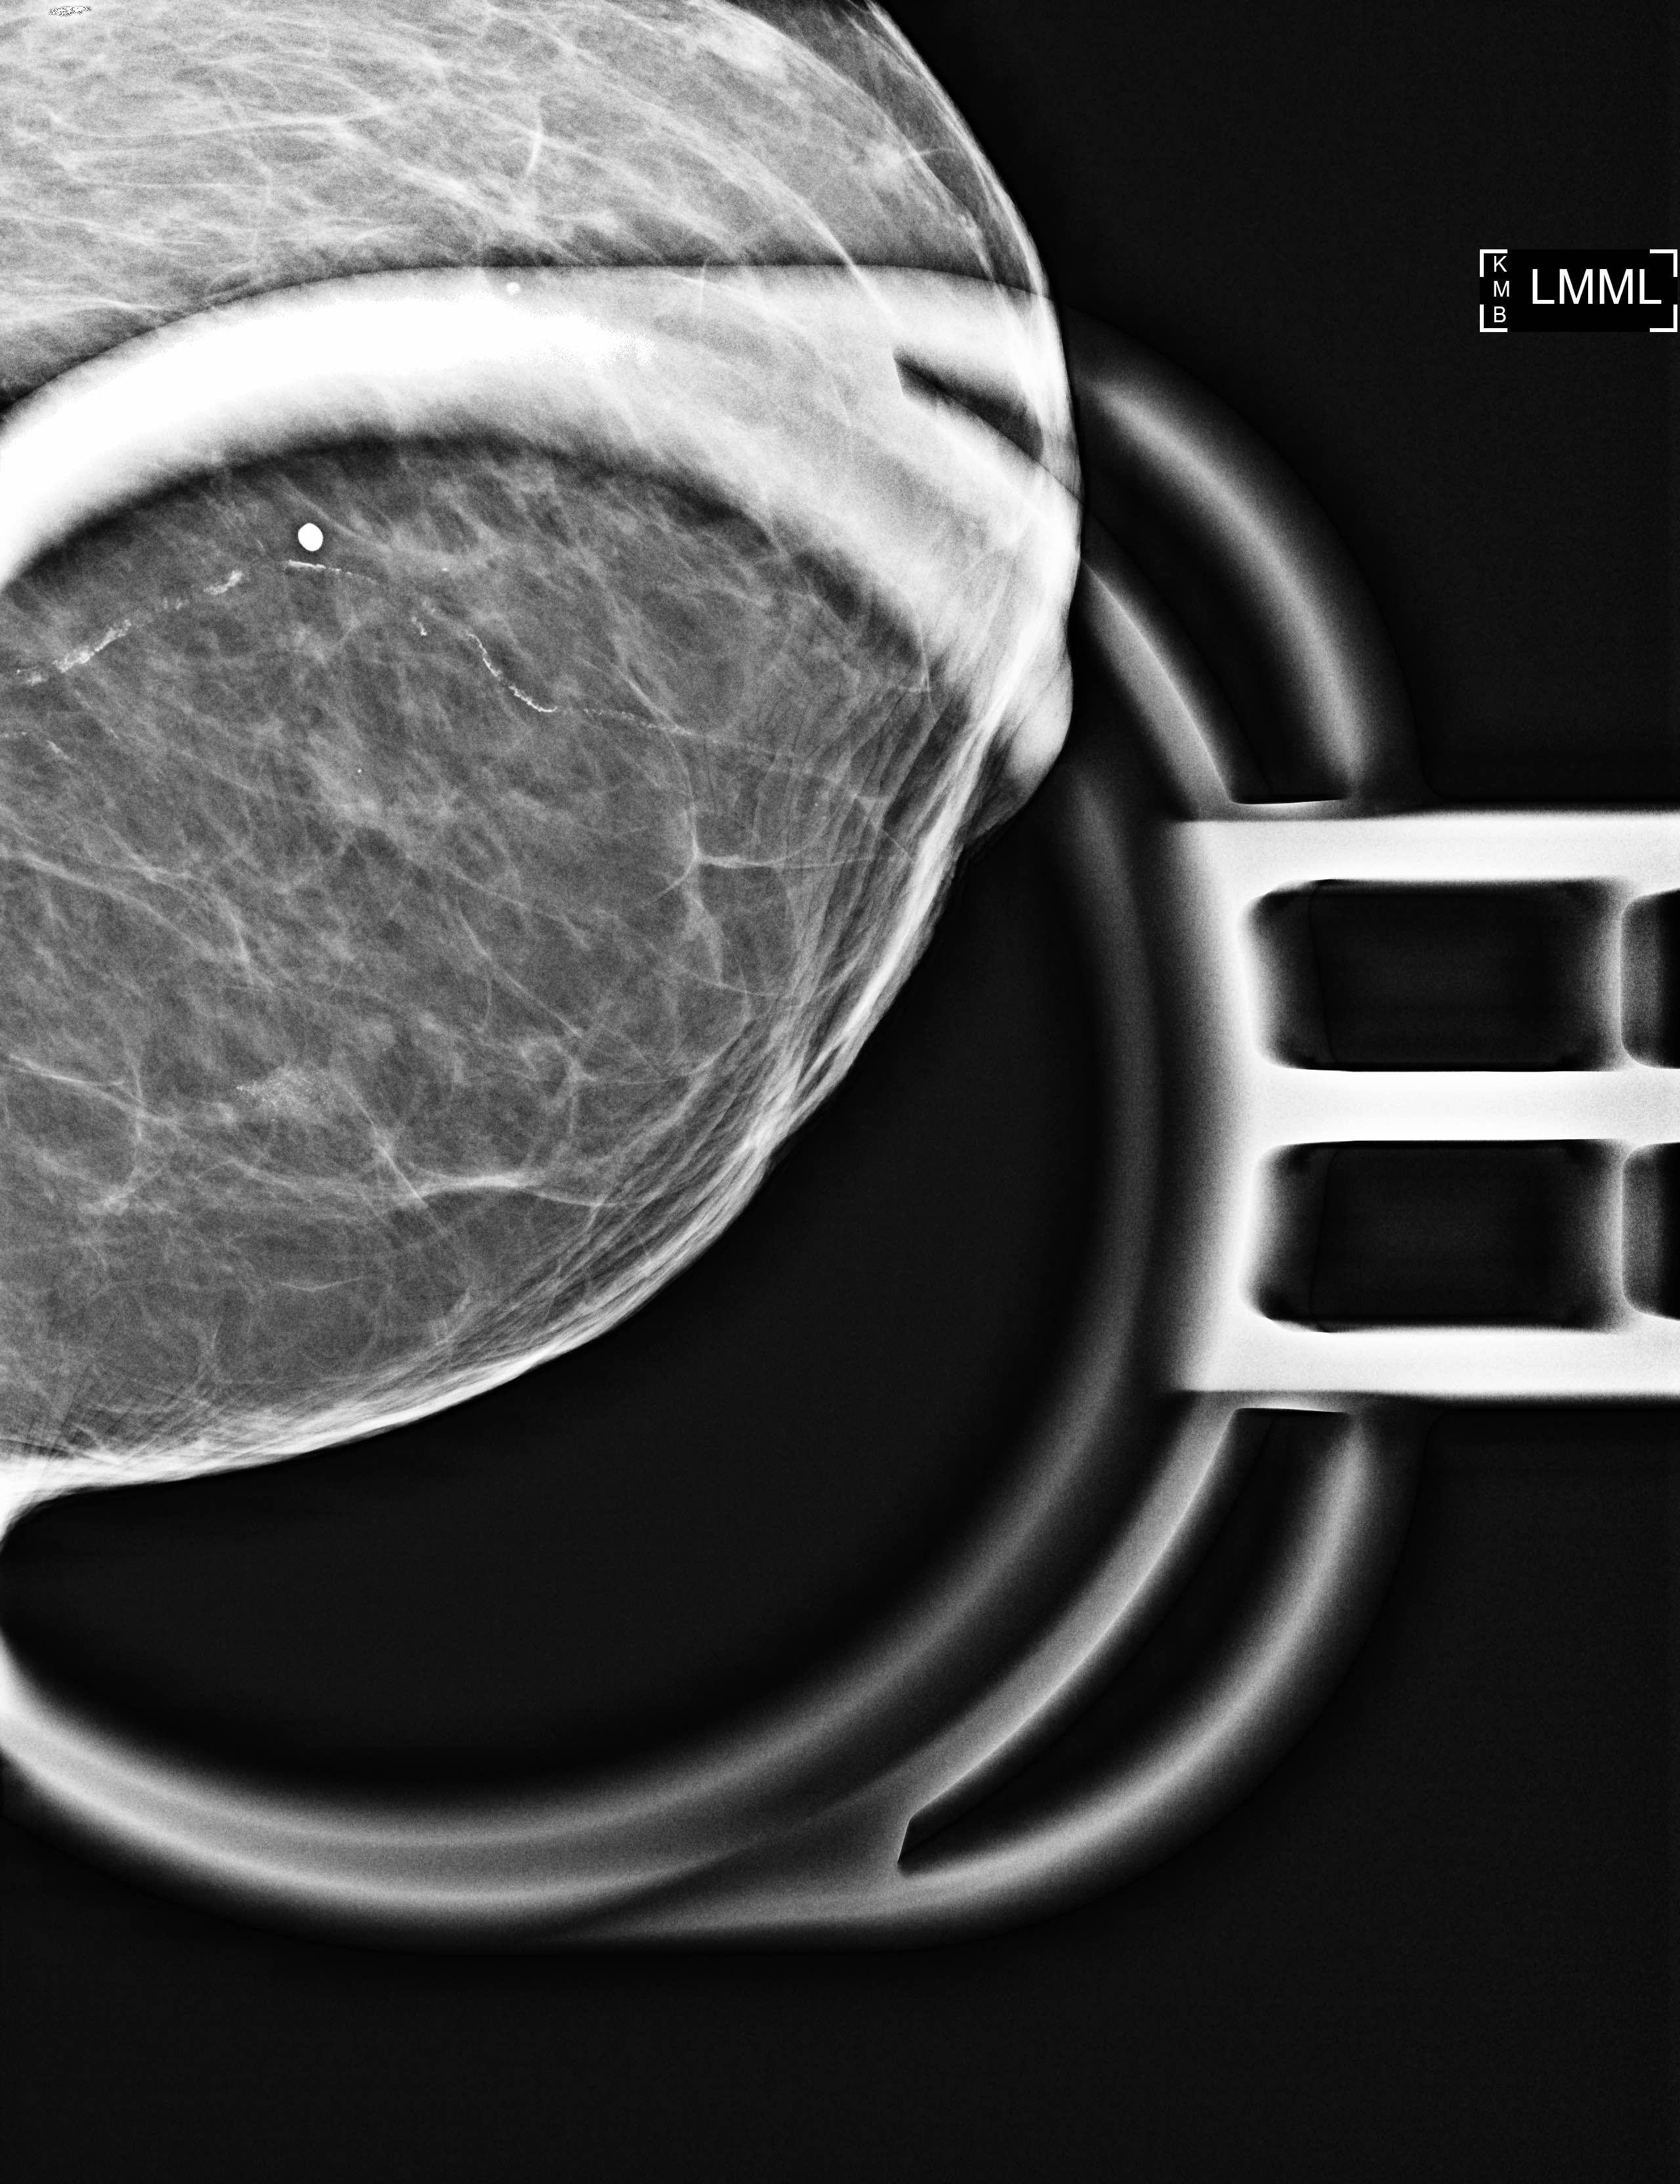

Radiology description

- Grouped amorphous calcifications on mammography (frequent) (AJR Am J Roentgenol 2011;197:740)

- No radiologic correlate / incidental (occasional)

A. Calcifications on mammography

Flat epithelial atypia (FEA) is typically diagnosed by stereotactic biopsy of mammographically detected intraluminal calcifications. Less frequently, it constitutes an incidental finding on biopsy or excision. It does not typically present as mass on imaging nor a filling defect on ductogram or galactogram.